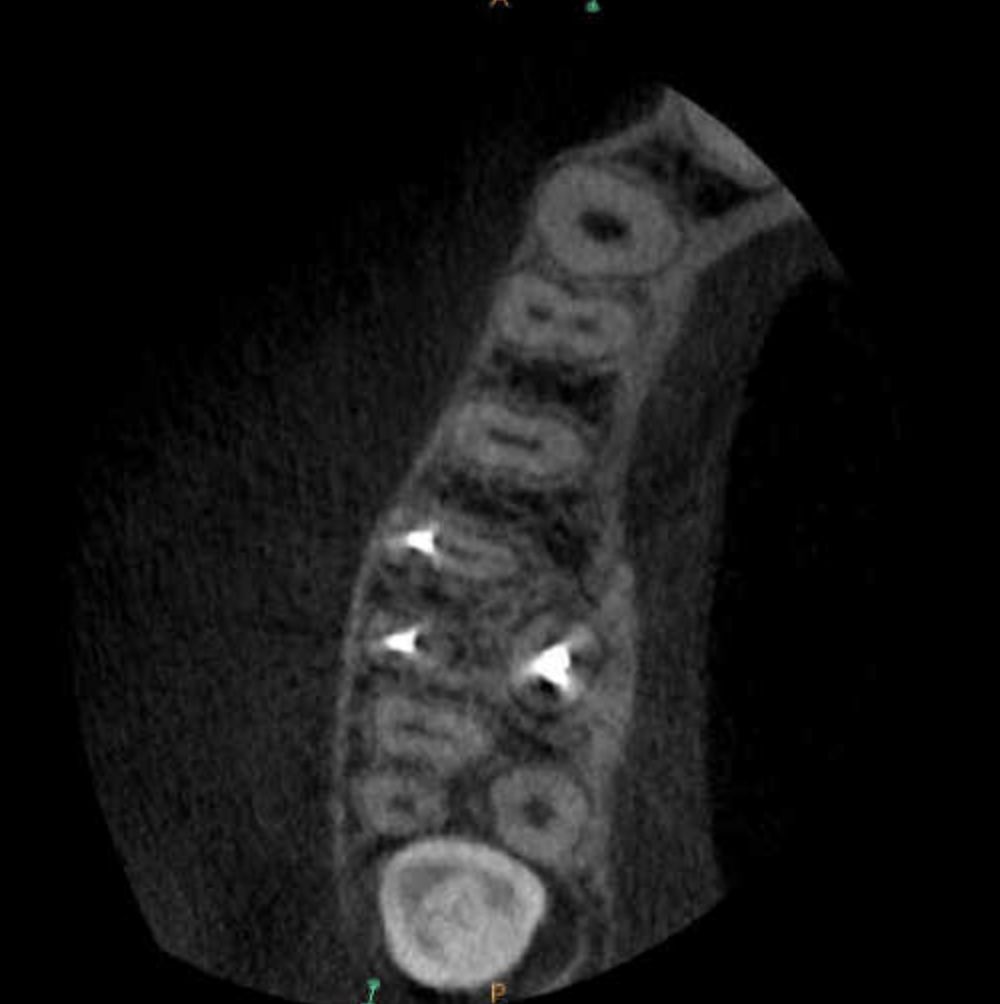

Molar gran curvatura bifurcación palatino